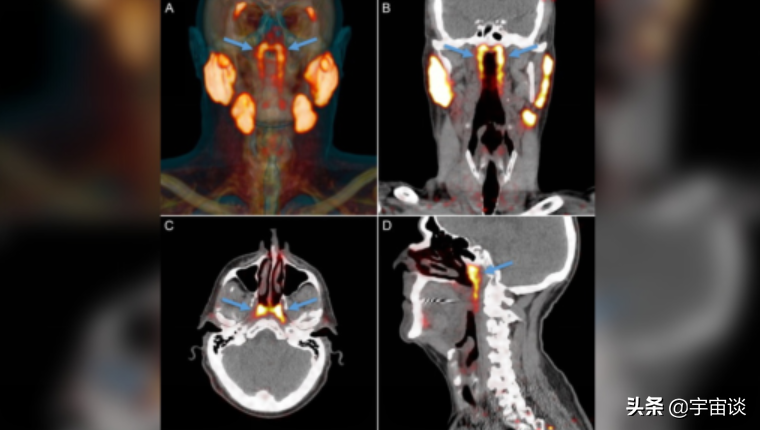

無獨有偶,在今年9月份的時候,科學家又發現了人體身上的另外一個新的器官,而這個器官在之前很長一段時間都沒有被發現,經過科學家反覆的研究證實這是一個唾液腺。與以往認知的三種唾液腺並不相同,那麼這個深處喉嚨深處的器官又有什麼作用呢?

當然之前科學家也知道喉嚨裡邊有這樣一個東西存在,但是始終認為這個是喉嚨的一部分。經過研究,卻發現這是人體的重要的一個器官,以後只要進行放射療法的喉癌以及頸部癌的患者避開這個區域,那麼會大大的提高治癒的可能。當然這個器官並不是進化得來的,而是每個人都有,這是人體的標配。